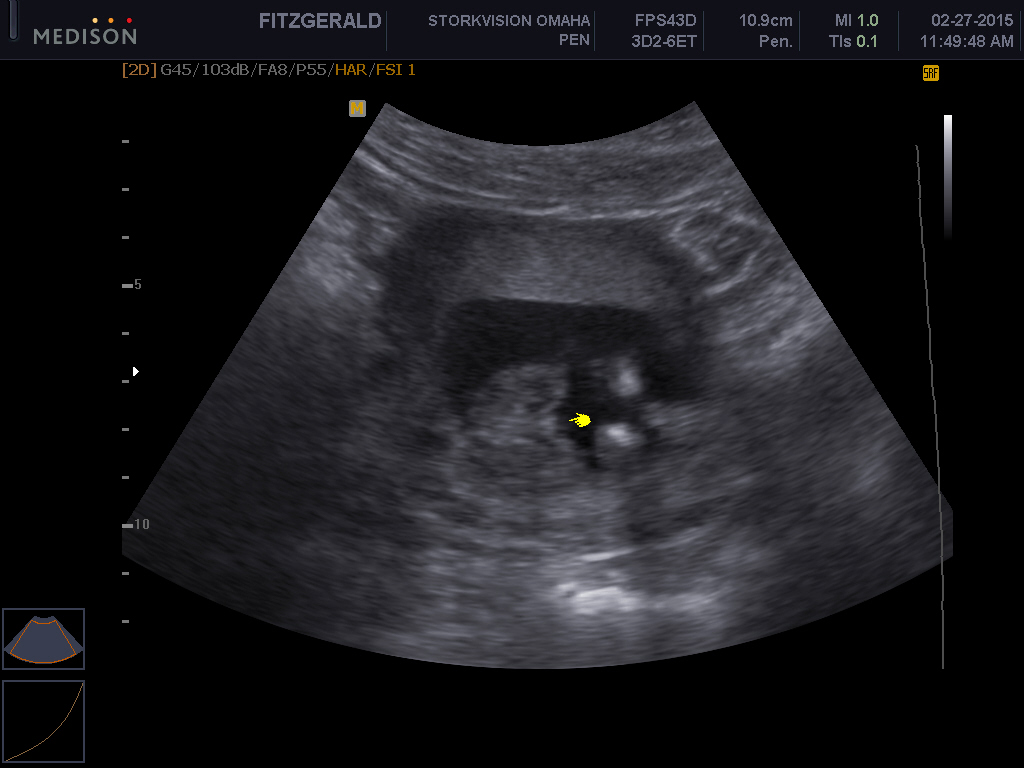

Attachment 23962Attachment 23963

Yes, girl.

definite girl!

16 weeks